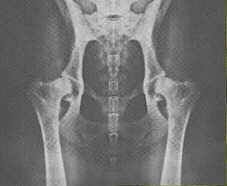

Links HD A, rechts HD E

Foto: Mit freundlicher Genehmigung des Schweizer Do-khyi Clubs